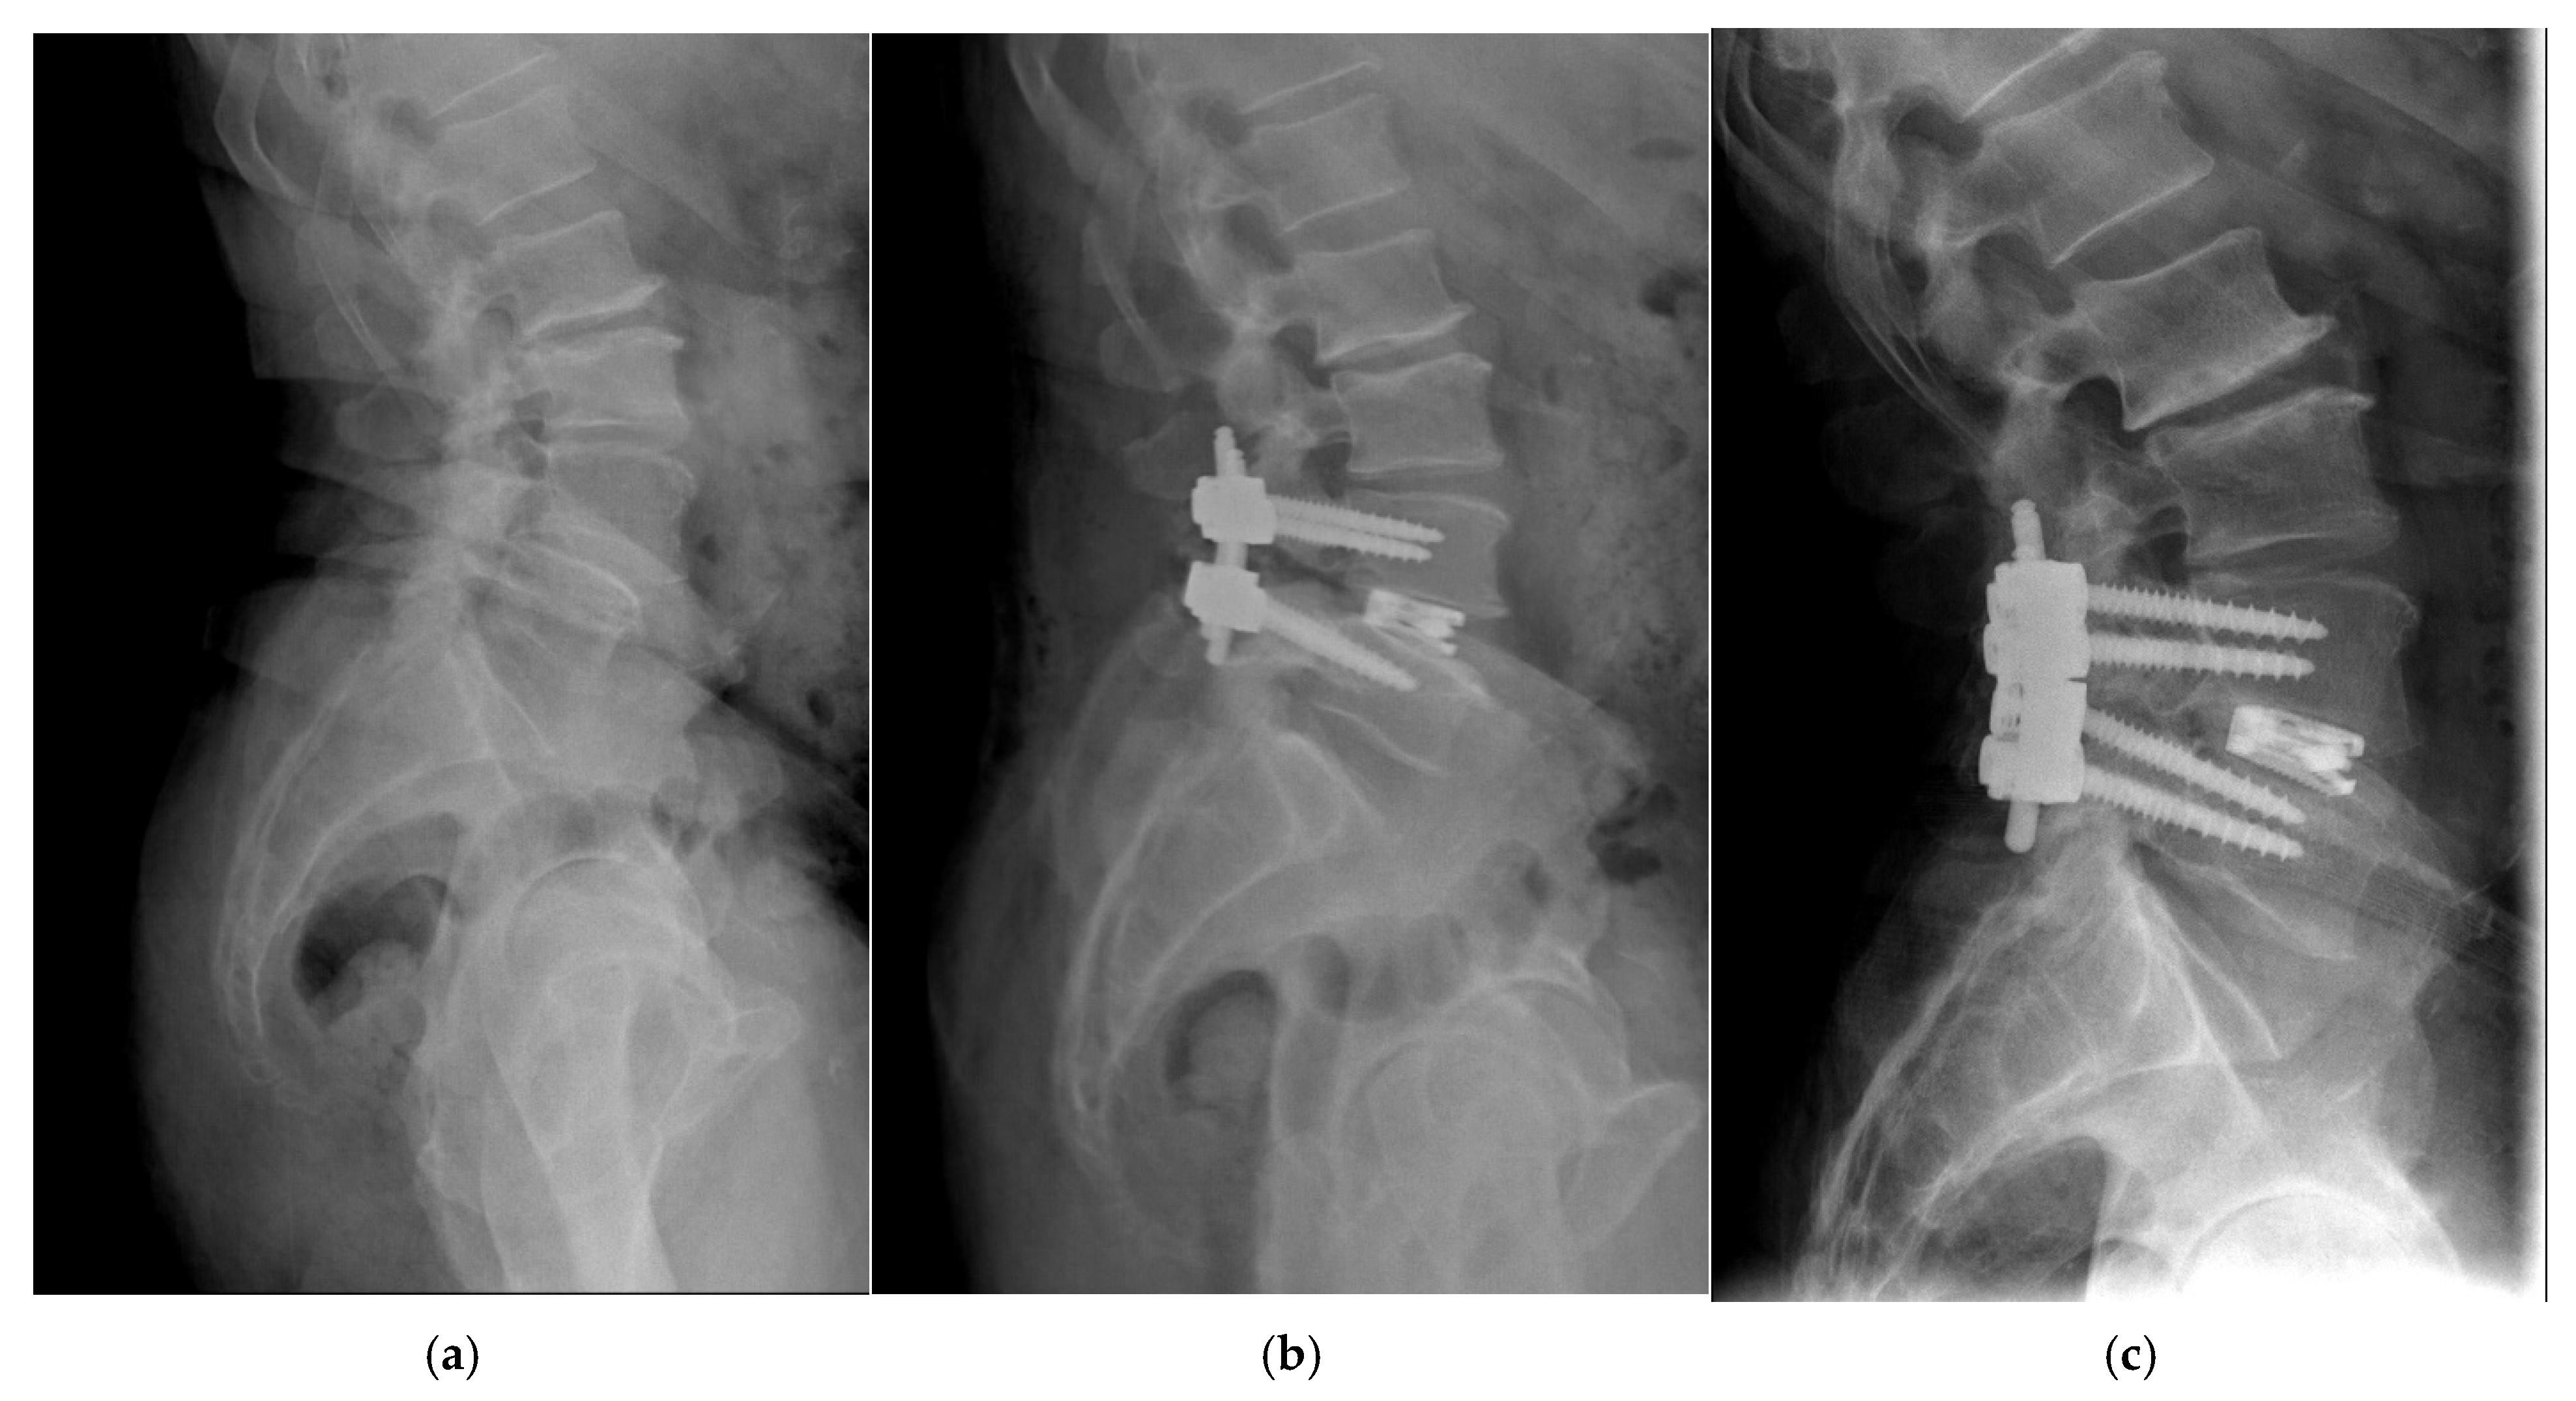

2.2. Surgical Procedures